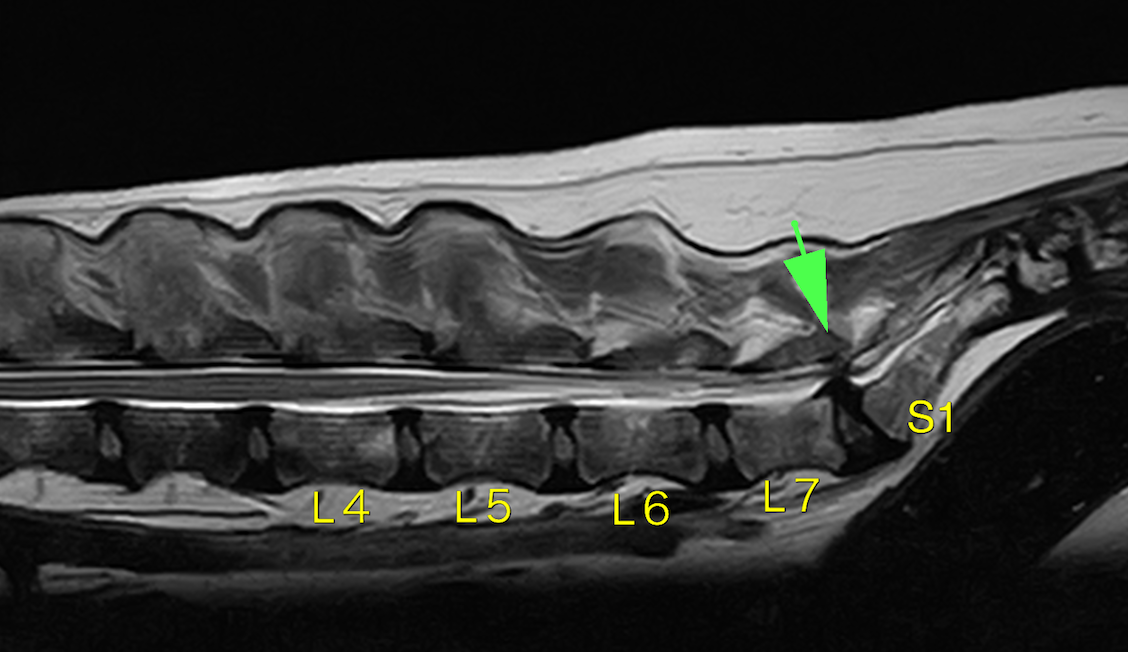

変性性腰仙椎狭窄症(DLSS・馬尾症候群)は第7腰椎と仙骨(人で言う尾てい骨)の間が何らかの原因で狭くなってしまい、そこを通る神経(馬尾神経)を圧迫してしまうことで、後肢麻痺などがおきる疾患です。原因は背側の黄色靭帯の肥厚や、腹側の椎間板による圧迫、仙骨の不安定性によるものなどがあります。それらにより神経が圧迫され腰の痛みが出ることが多く、さらに尻尾が動かしにくくなったり、後ろ足がしびれたり立てなくなったり、ひどくなると排尿排便困難になることもあります。

触診や神経学的検査、レントゲン検査で仮診断し、確定診断にはMRI検査が必要になります。

L7とS1(第7腰椎と仙骨)の部分での神経圧迫が確認できました。治療には内科的に痛みを取る方法や、外科治療がありますが根本を解決するには現在のところ外科治療しかありません。 手術では背中からアプローチし、骨と靭帯を除去したのちに腹側の圧迫があればそれも除去します(減圧)。その後に腰を曲げ伸ばした状態でスクリューと骨セメントを利用して固定します。

L7-S1の間に圧迫が見られます。矢頭部が圧迫物質です(黄色靭帯の肥厚がメイン)。